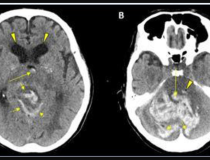

This photo gallery shows the variety of radiological presentations of COVID-19 (SARS-CoV-2) in medical imaging, including computed tomography (CT), radiograph X-rays, ultrasound, echocardiograms and magnetic resonance imaging (MRI). The radiology images show examples of typical COVID pneumonia in the lungs and the numerous complications the virus causes in the body in multiple organs, including the brain, kidneys, heart, abdomen and vascular system.

Ultrasound, especially hand-held ultrasound imaging devices, have become a primary imaging modality for novel coronavirus because of the ease to bag the device and sterilize it after use. CT and mobile X-ray systems are also used as front-line imaging systems for COVID-positive or suspected COVID patients.